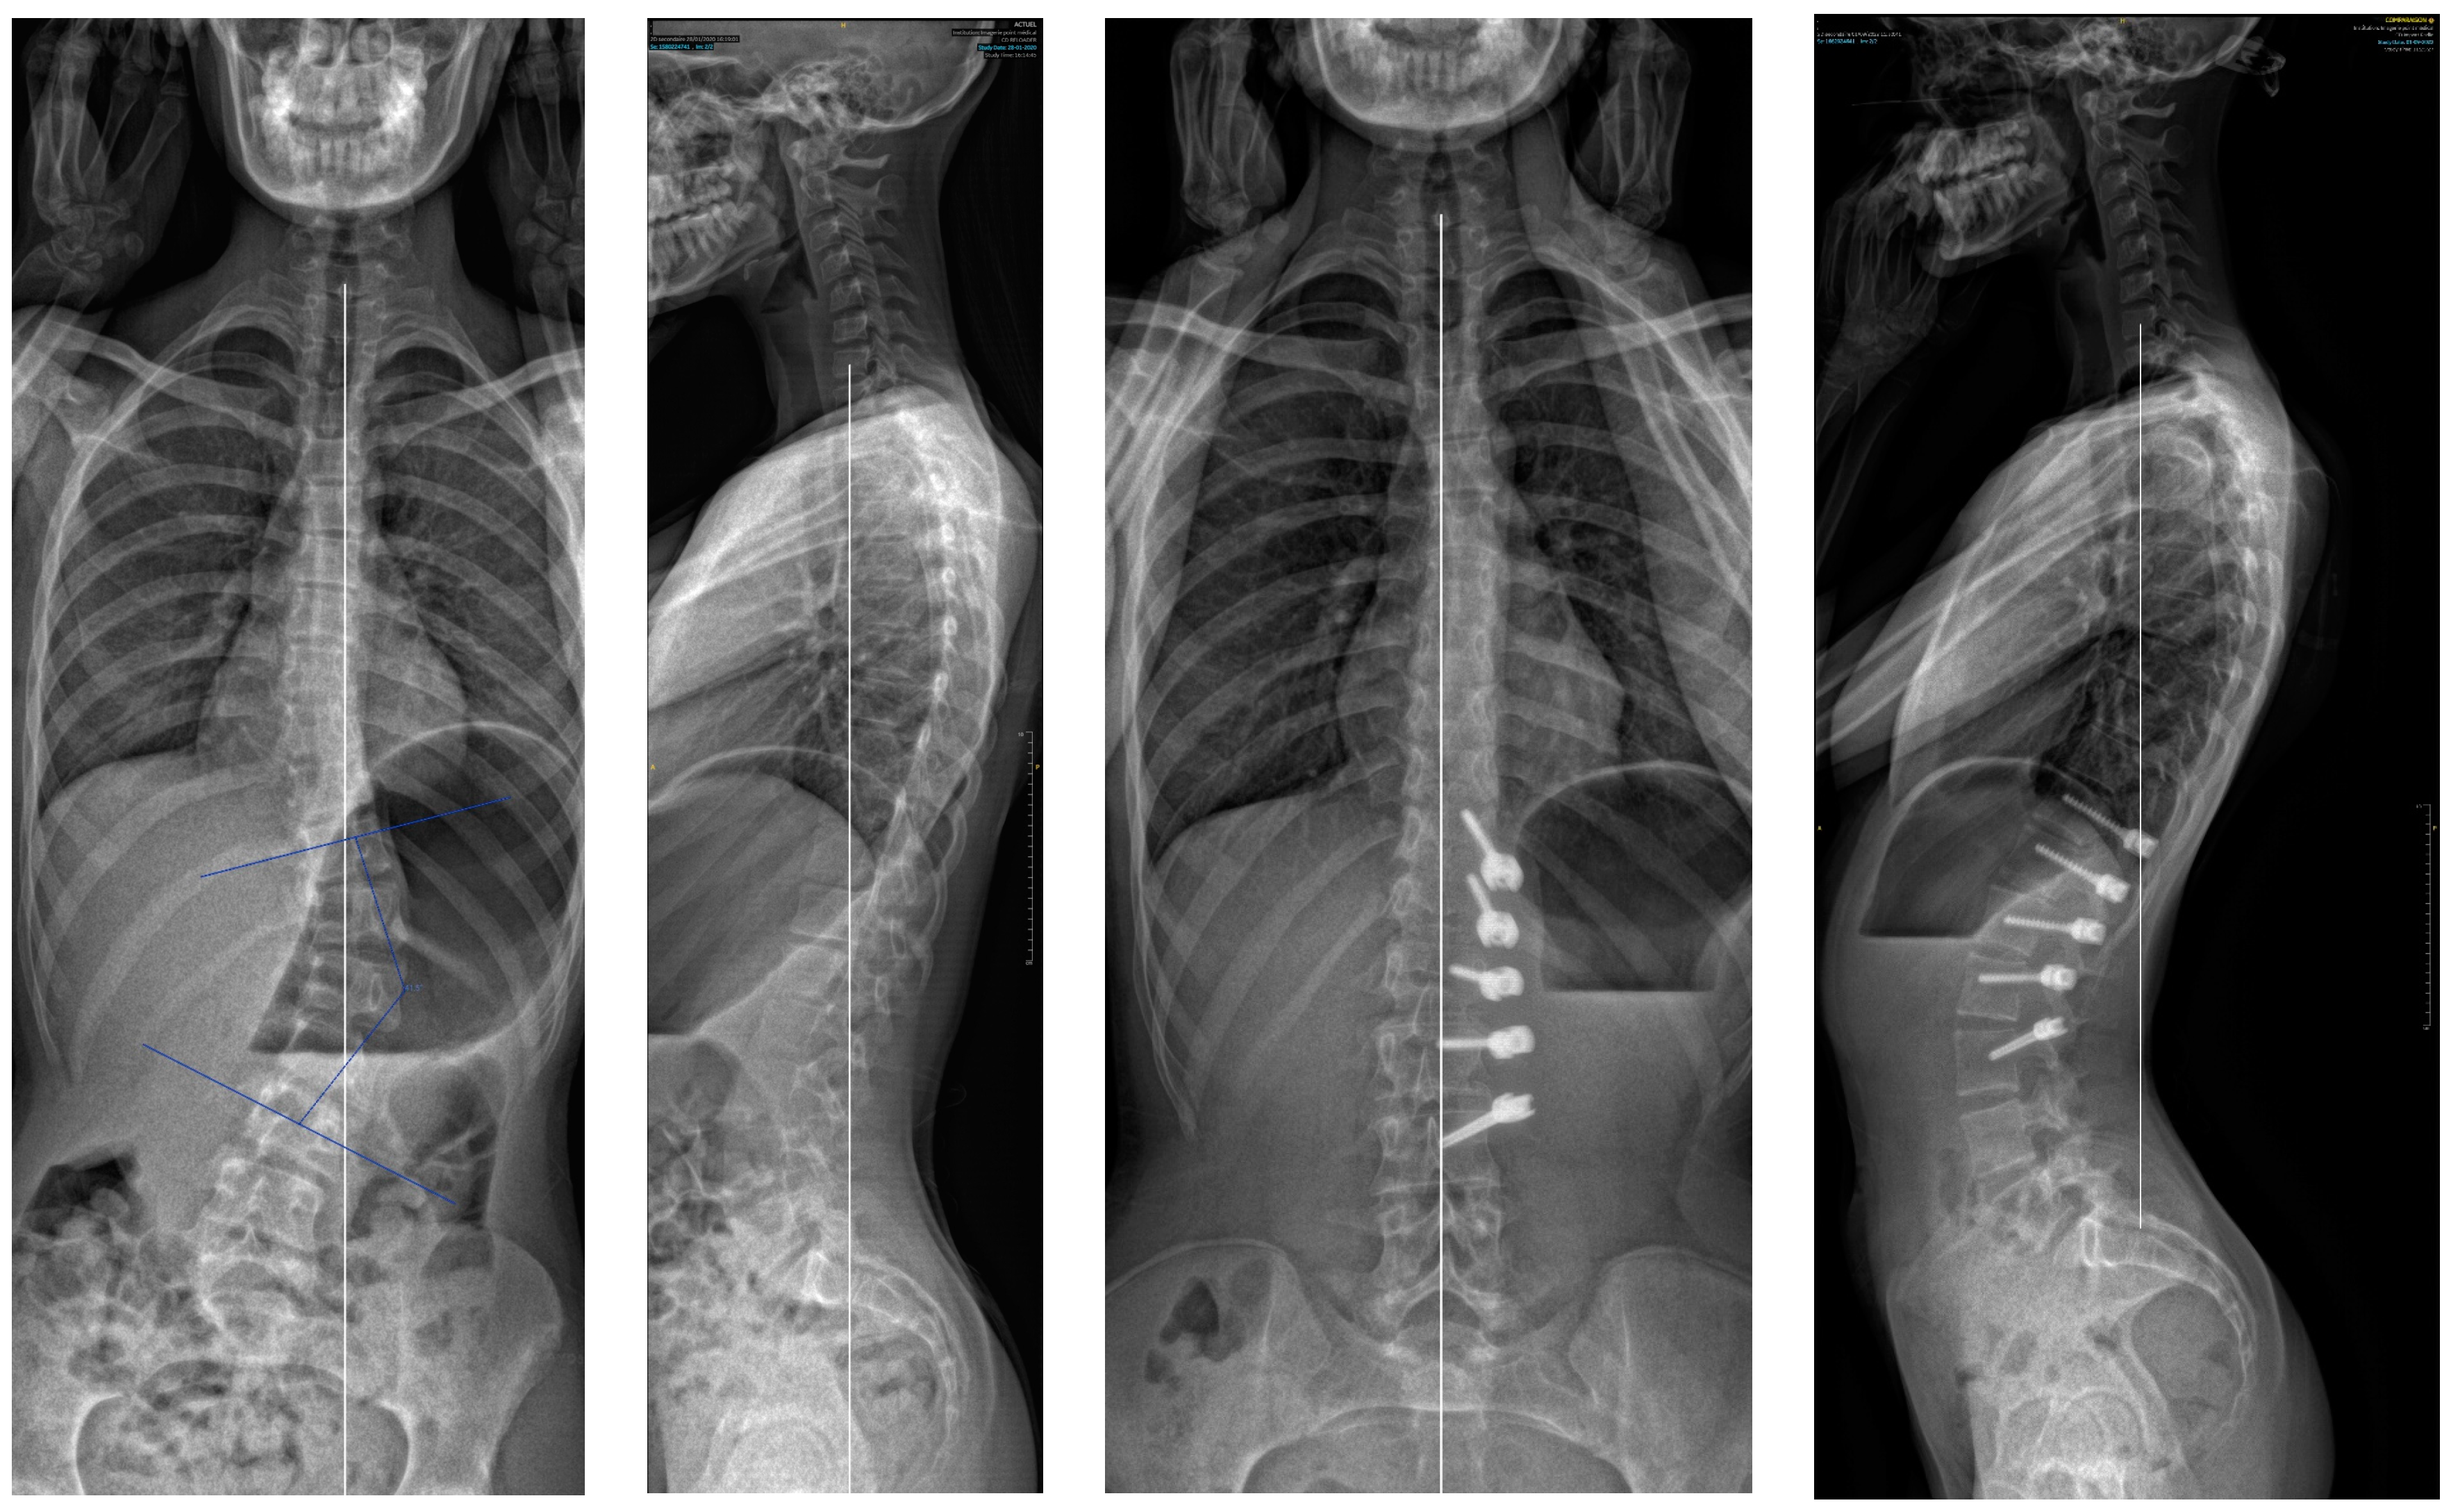

If we analyse the correction and look first at the results after surgery and before, there was an initial improvement of the major curve from 43.9° to 20.3° (54%) due to the “brace effect”, as was observed in other studies [1]. But if we compare the results after surgery and at two years (Figure 7), it seems there was not much correction by growth modulation as described in Anterior Vertebral Body Tethering [1,17,18]. Indeed, there was an amelioration of 7.1° (35%), but it was not statistically significant. This result was unexpected, and must be investigate with studies involving more patients as there was clearly a growth modulation on several cases, leading to an overcorrection. An explanation could be the average old age of the patients with not enough growth remaining.

A 13-year-old female, Risser 0. The lumbar curve measured 38° pre-operatively, improved to −10° (slight overcorrection) at two years. In this case, there was an augmentation of both the lumbar lordosis (40° to 58°) and thoracic kyphosis (22° to 37°).

The material itself is also important. Screw breakage only occured with the CTJ+™ material from Neurofrance® and always on the proximal screw (Figure 8). Indeed, these screws had a very wide thread and a thin core, making them probably less strong for the same diameter. No breakage occurred with the Braive™ or the Reflect™ screws. Anyway, these breaks did not change the outcome of the concerned patients.

A 13-year-old female, Risser 2. The main curve measured 37° pre-operatively and −18° at 2 years. The overcorrection did not change the good result. In this case the secondary curve improve from 23° to 0°. Note also the broken screw.

As previously mentioned, a new surgery technique with posterior fusion has been necessary in three cases (13.6%); this rate is comparable to other studies [1,29]. In two cases, it was due to a lack of correction (Figure 9) in patients with an initial Cobb angle probably too important (>50°): this seems to be the limit for the Cobb angle for Posterior Vertebral Body Tethering unless the spine is very flexible. The other one was an overcorrection in a patient: Risser 0, Y cartilage open and a very flexible spine who was probably operated on too soon.

A 15-year-old female, Risser 3 measuring 50° pre-operatively and 44° post-operatively; became worse, requiring a posterior fusion.